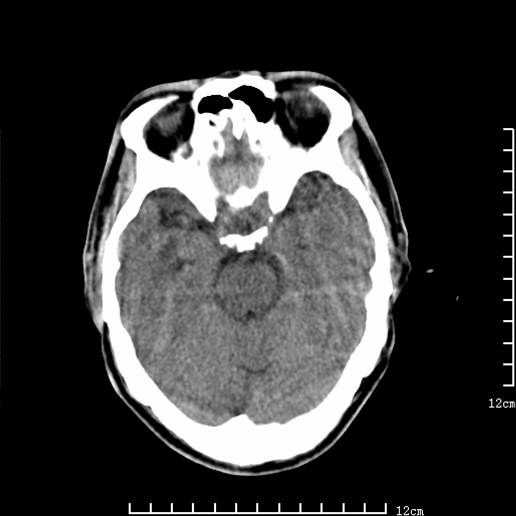

以下图像分别是3月25日凌晨及下午图像、3月27日、4月16日的ct图像。

3月25日下午